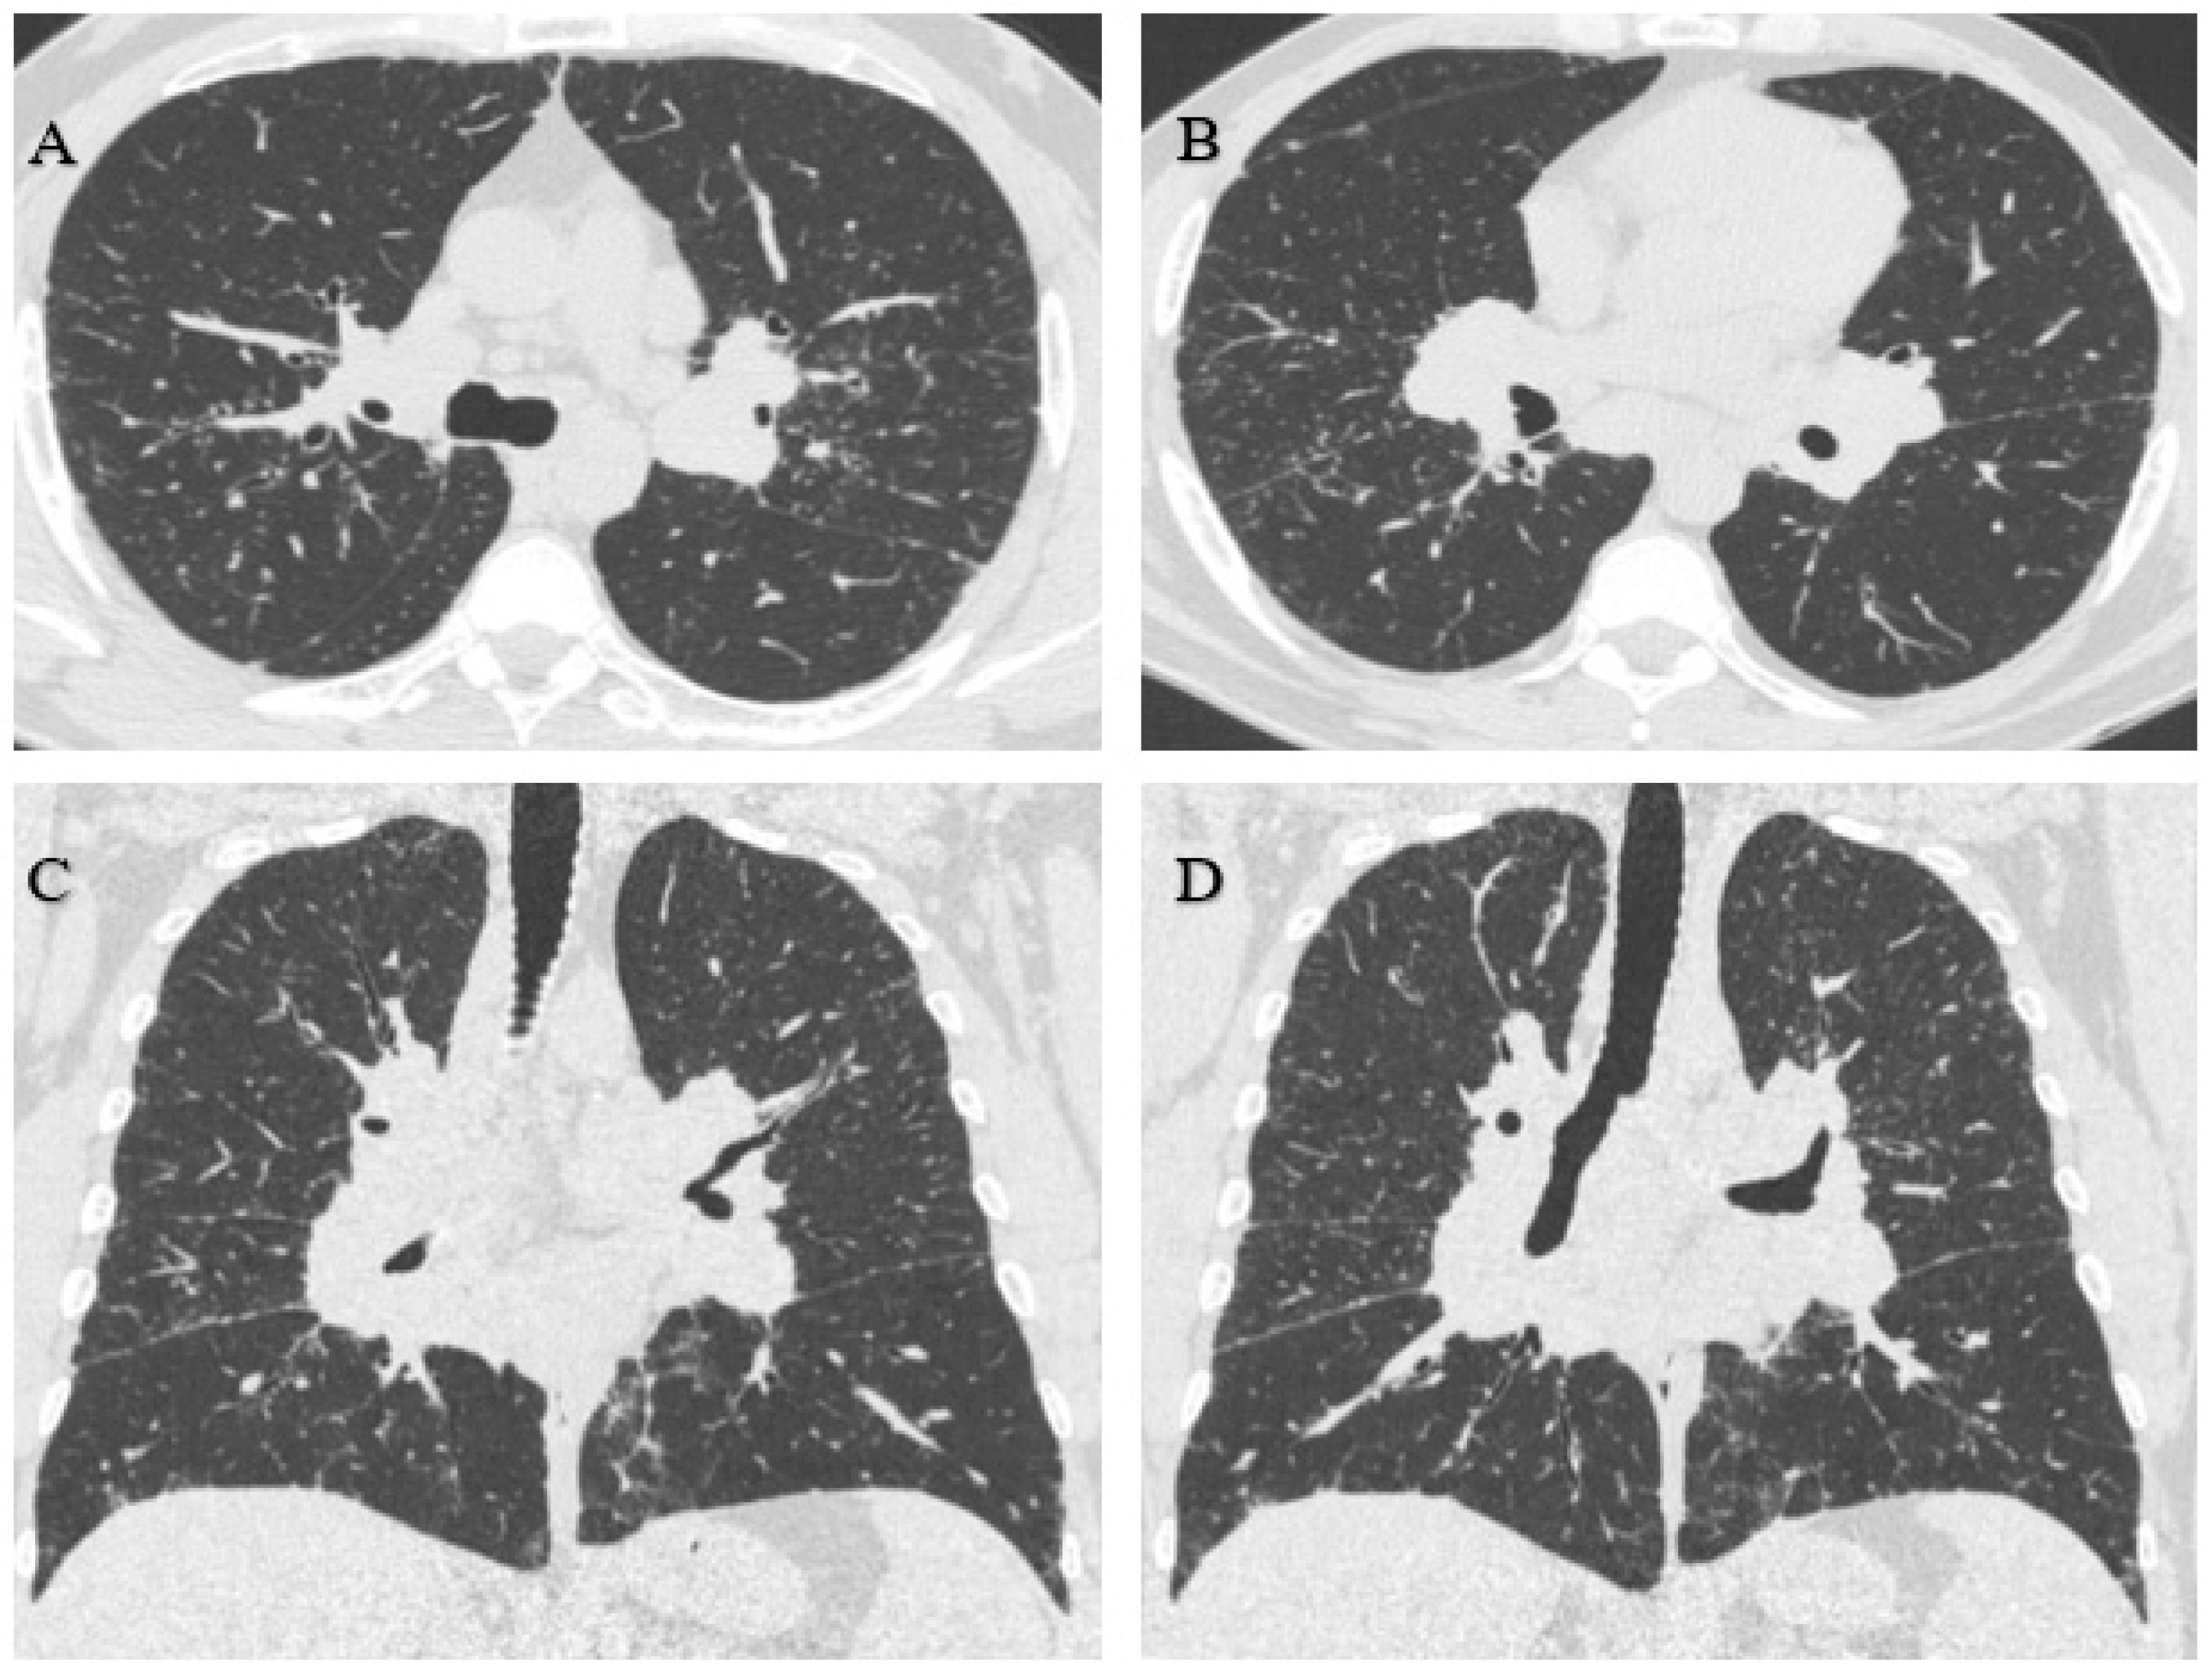

3.1.1. Case 1